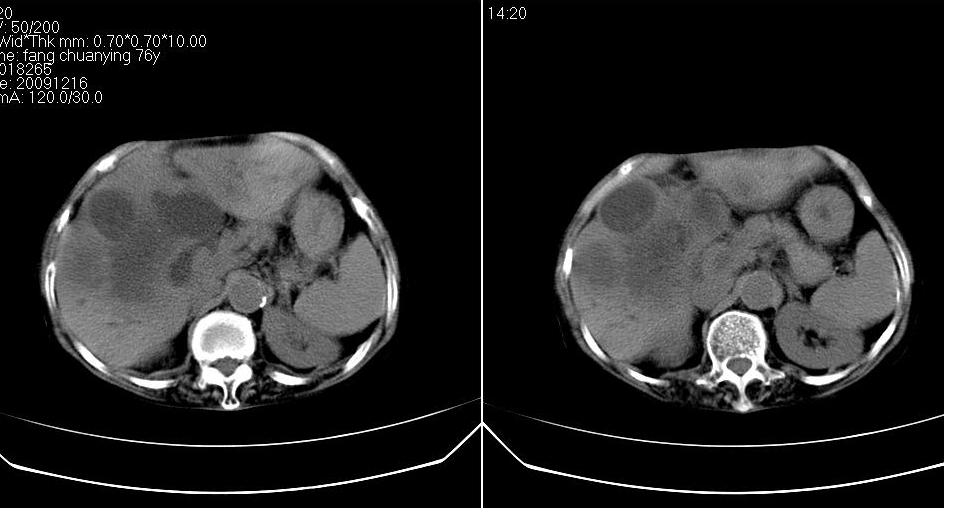

标题: CT23701:上腹部CT平扫

女 76岁,腹痛十余天。

肝癌、肝囊肿。

肝脓肿,腹主动脉硬化,建议增强

胆管细胞癌合并感染?建议增强协诊。

肝癌伴肝内胆管扩张,建议增强.

肝内胆管扩张,综合考虑胆管细胞肝ca!

考虑肝癌(胆管细胞型?)并肝内胆管扩张。